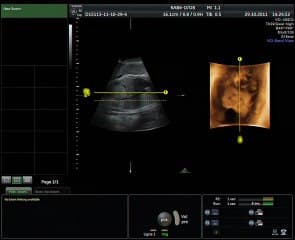

Comme d'habitude Bernard BENOIT nous éblouit avec des images normales et pathologiques en Echographie 2D et 3D de l'embryon entre 8 et13 SA. Focus particulier sur la face et le cerveau avec des diagnostics indispensables au 1 et T comme l'holoprosencephalie alobaire, l'acranie , le micro-retrognathisme , la poly malformation et parfois les fentes.

Comment donner un meilleur diagnostic de la fente avec pour but de collecter un maximum d'informations utiles pour le chirurgien. L'auteur décrit la technique d'acquisition en 3D avec une déflexion de la tête, l'usage d'un magic cut. Considérations très techniques qui peuvent bien sûr paraître obscures pour les non-opérateurs du 3D.